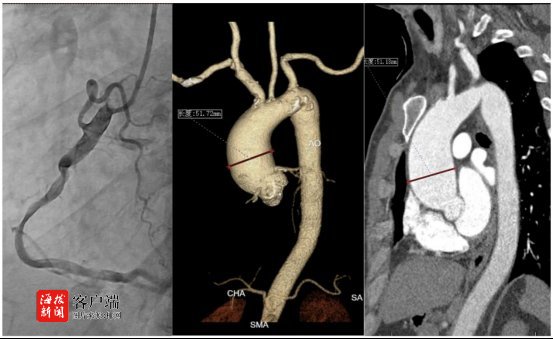

入院后,心外科團隊迅速為陳先生進行了詳細檢查評估,。在嚴飛主任團隊,、符川醫(yī)生(心臟超聲)、洪超醫(yī)生(主動脈三維成像)以及心內科冠脈造影團隊的緊密協(xié)作下,,陳先生的病情很快明確:

1主動脈瓣回聲增強,,重度狹窄(瓣口面積僅0.8cm²,遠低于正常值),;

2升主動脈瘤樣擴張(最寬處直徑達52mm,,遠超正常上限);

3.右冠狀動脈中段存在嚴重狹窄(60—70%),,近段狹窄30%,。

綜合評估后,,團隊制定了精密的手術方案:同期進行“主動脈瓣置換+升主動脈置換+冠脈搭橋術”,。